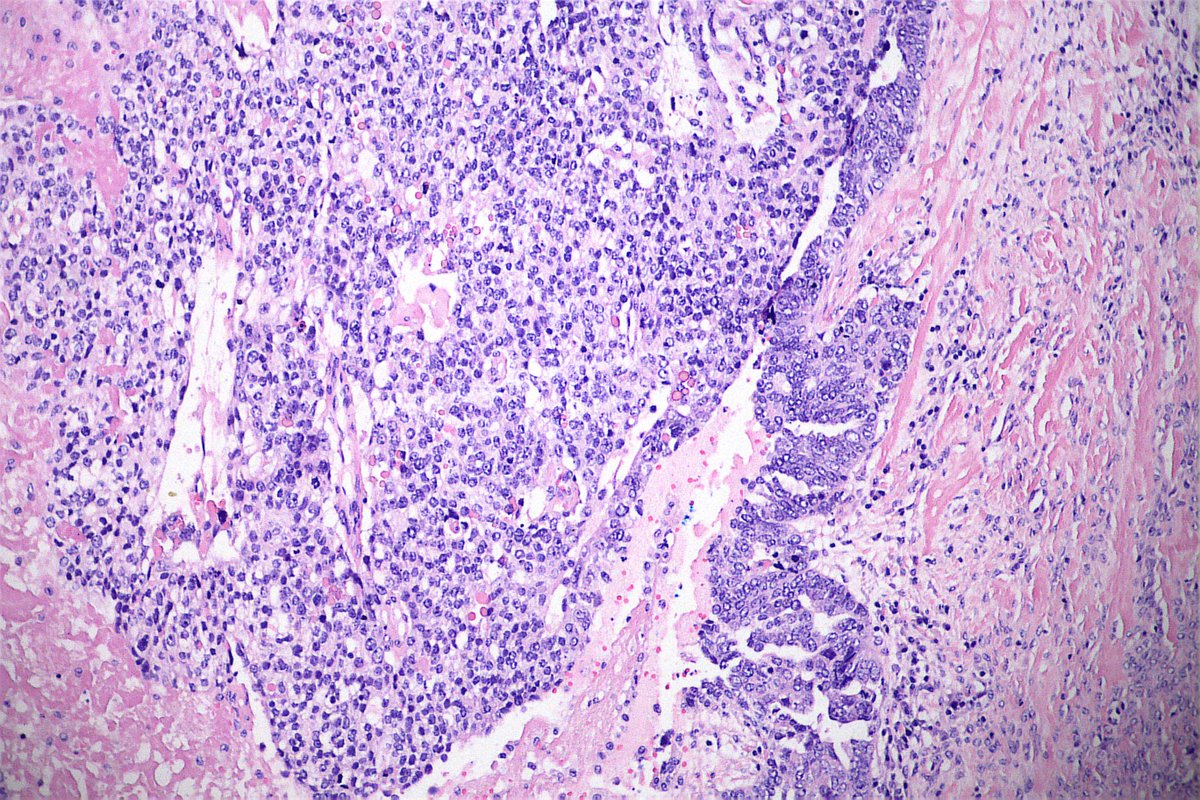

#Gynpath #Surgpath #pathresidents #Pathtwitter Some images of an endometrioid-type adenocarcinoma of the ovary in a 60-year-old woman. Mismatch repair proteins MLH1 and PMS2 show loss of staining (note negatively-staining tumor cell nuclei, with positively-stained stromal

Some images of an endometrioid-type adenocarcinoma of the ovary in a 60-year-old woman.

Mismatch repair proteins MLH1 and PMS2 show loss of staining (note negatively-staining tumor cell nuclei, with positively-stained stromal